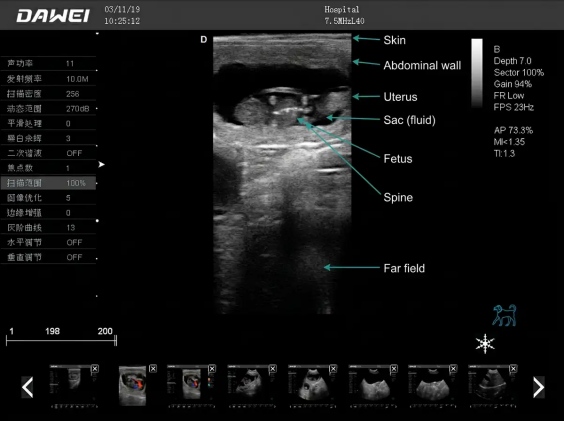

La ecografía para diagnosticar el embarazo temprano en perras permite detectar el saco embrionario tan pronto como a los 20 días después del apareamiento. La precisión del diagnóstico precoz del embarazo en perras, entre los 21 y 25 días posteriores al apareamiento, puede alcanzar el 86%. El uso de sistemas de ultrasonido veterinario para detectar el embarazo en perras y guiar la reproducción animal es un método seguro, fiable y práctico.

3. Para realizar una ecografía en un perro, se puede utilizar una sonda microconvexa de 6,5 MHz para comenzar en la sínfisis púbica, detectar la vejiga y luego avanzar hacia la región uterina en ambos lados, moviendo la sonda a medida que avanza para obtener imágenes en diferentes ángulos.

¿Qué equipo se utiliza para la ecografía de gestación en perras?

Los veterinarios suelen utilizarEcografía en modo B (en tiempo real)para el diagnóstico de gestación canina. Para la ecografía de gestación canina, las clínicas suelen adaptar el sistema a su flujo de trabajo; algunas prefieren unEcografía veterinaria básica para ordenador portátil

(por ejemplo, MU10), otros necesitan unescáner de ultrasonido veterinario portátilpara uso sobre la marcha (por ejemplo, Slite), y algunos eligen un modelo de nivel básico.Ecografía Doppler color para mascotassistema (por ejemplo, L30i) para necesidades de imagen más amplias.

- Muchos perros: un transductor de ~5,0 MHz puede funcionar bien (referencia general en la literatura veterinaria).

- Razas miniatura / perros muy pequeños: una frecuencia más alta (por ejemplo, ~7,5 MHz) puede mejorar la resolución.

- Las sondas microconvexas son populares para la exploración abdominal en animales pequeños porque son más fáciles de posicionar.